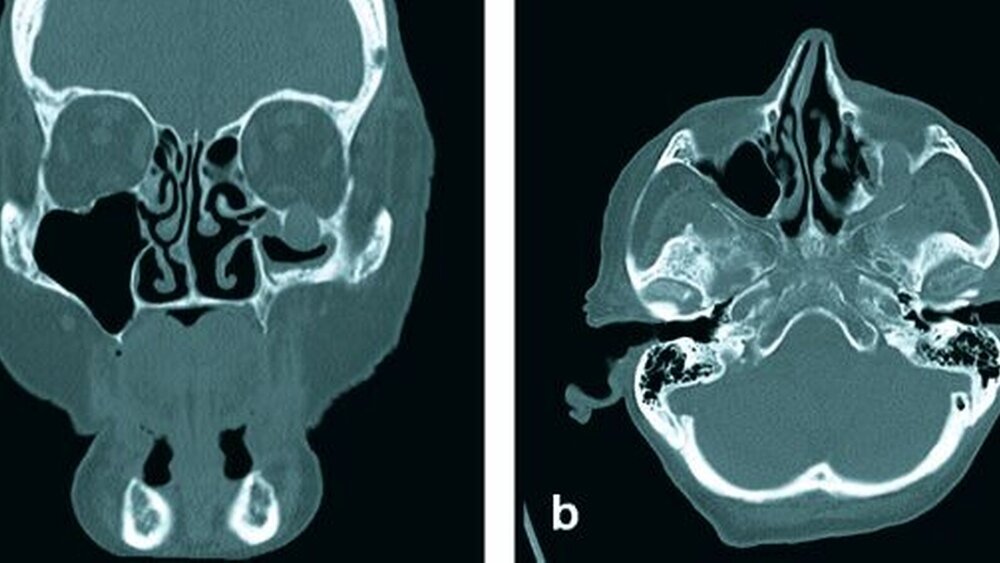

Bei Verdacht auf ein Rezidiv des vordiagnostizierten primitiven neuroektodermalen malignen Tumors wurde zur weiteren Abklärung im Rahmen des Restagings eine Computertomografie des Gesichtsschädels und des Halses veranlasst. Diese ergab einen ausgedehnten Tumor, der sich vom Wangenbereich entlang des Nervus infraorbitalis über die Fissura orbitalis inferior bis zur Schädelbasis wachsend darstellte. Der knöcherne Kanal des Nervus infraorbitalis zeigte sich massiv aufgetrieben (Abbildung 2). Die übrigen, im Rahmen des Stagings veranlassten Untersuchungen (Röntgen-Thorax, Oberbauchsonografie) ergaben keinen Hinweis auf das Vorliegen von Filiae.